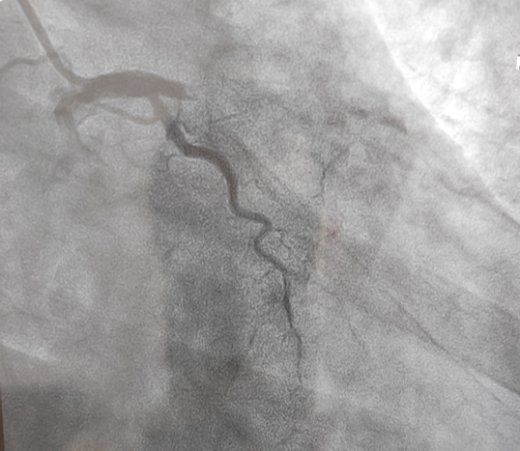

立即啟動綠色通道,急診冠脈造影,結果顯示前降支近段閉塞,血栓負荷較重,先后給予血栓抽吸及球囊擴張,血流恢復正常。李桂武主任和劉興剛主任發(fā)現(xiàn)患者近段狹窄達70%,且中遠段嚴重狹窄伴鈣化,此時不適合同期植入支架,如植入支架可能會引發(fā)血管破裂危及生命。當務之急是快速評估出患者是否可以下手術臺,選擇擇期進行處理,但僅根據造影結果又很難做出判斷,李桂武主任和劉興剛主任快速討論研究最后一致決定,給予患者行冠脈OCT檢查,明確病變性質。

經OCT檢查結果顯示:前降支中段鈣化,內膜光滑,最小管腔面積僅為1.19 mm2。近段斑塊破裂,可見血栓影,最小面積為2.63mm2??蛇x擇先進行抗栓治療,擇期處理冠脈病變。這讓張先生懸著的一顆心終于放下來。